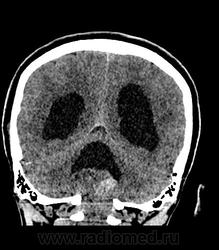

Девушка 30 лет. Поступила с диагнозом Эпилепсия. Неоднократные синкопы, начавшиеся после родов. Роды в начале марта, все благополучно. После родов, как-то так плохо все,шатает, голова болит. Через месяц обратилась в республиканскую больницу, выполнена кт- смешання гидроцефалия. Пролечили и выписали с диагнозом Дистония. Как-то так.

-признаки интравентрикулярной окклюзи выходных отверстий 4 желудочка, с резким расширением всех отдела желудочковой системы.

-межполушарная,латеральные щели и субарахноидальные пространства значительно уменьшены в объеме за счет увелиения желудочков и отека мозга

-истонены кости основания черепа,усилен рельеф внутренних костных пластин,углублено и расширено турецкое седло,опускание СЧЯ

-ствол и продолговатый мозг в дорсальном отделе уплощены,смещены вентрально

-в полости 4 желудочка объемное образование с учсатками кровоизлияния, с распространением каудально, признаки вклинения миндалин в БЗО,большая цистерна и САП кранио-вертебрального перехода не прослеживаются.